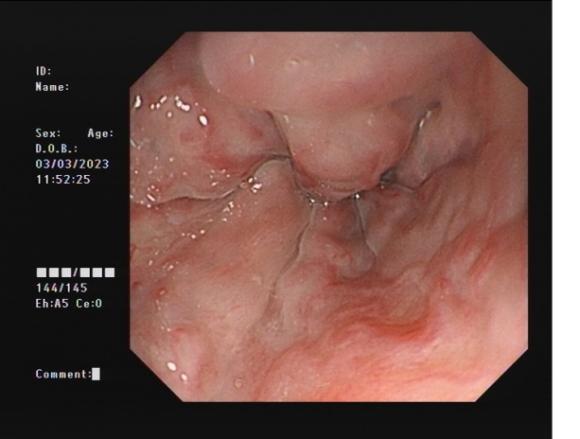

c617422923344d8ab1fe329c78d7814e.Jpeg5755b6aa8ded4797a794f5f01a4f88e6.Jpeg

食管靜脈曲張             內(nèi)鏡下套扎術(shù)

食管靜脈曲張?zhí)自g(shù)(EVL):治療食管靜脈曲張、胃底靜脈曲張破裂出血、藥物止血無(wú)效者;既往有食管靜脈曲張破裂出血史者預(yù)防再出血。